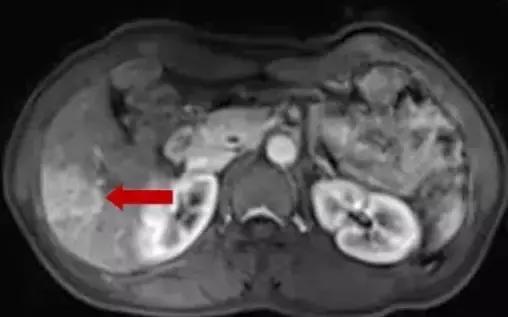

肝右后叶转移灶

术后50天复查CE-MR,肝转移瘤消融后病灶未见明显活性。